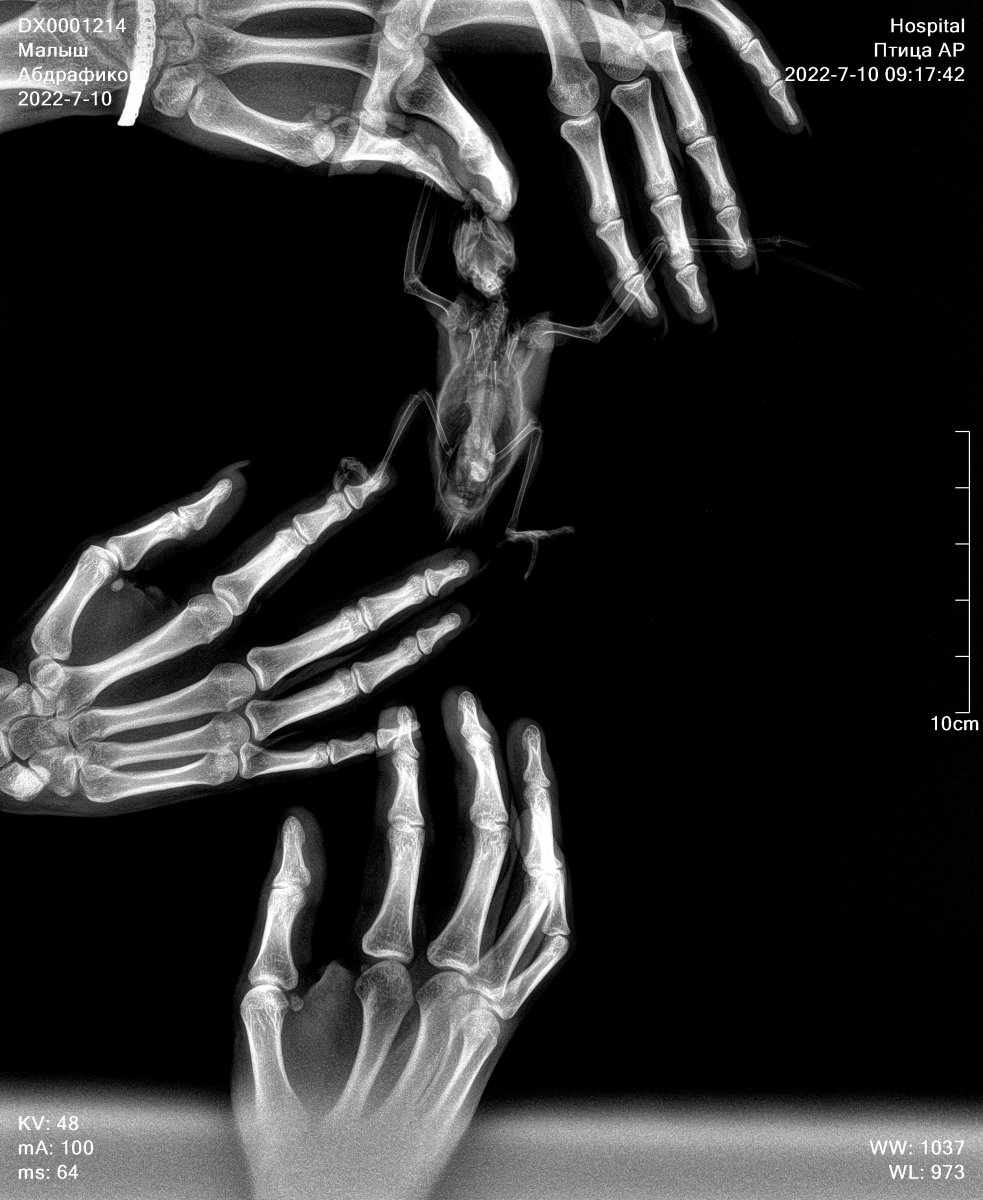

Добрый день ! Заболел попугай ,зовут Малыш, можно сказать заметили симптомы три дня назад. Первый день мотал головой и выкидывал круглые зерна (так понял рвота была ), повезли на следующий день на рентген , ветеринар сходу сказал что исход неблагоприятный и у него Мегабактериоз, выписал три препарата пить нистатин, флоконазол и антибиотик амфотерцин В суспензия ( но данного лекарства не нашли , и вроде как завоз запретили в Россию. Второй день пропал аппетит и почти перестал воду пить. Мы начали его кормить со шприца сами, делаем каши с фруктами , потому что сказали так кормить сейчас уже и лекарства давать как прописали (нистатин и флоконазол).Держим сейчас в клетки , так как есть ещё попугаи. Постоянно глаза закрывает и шатается , бывает дергает , держим под лампой нагревания. Вчера заметил что хочет корм кушать твёрдый , все ищет его , но ему как сказали нельзя сейчас . В общем ветеринару данному почему-то доверия нет , как нас встретил сходу и ничем толком не помог может сказать … просто сказал плохо все , есть дорогие препараты , но скорее всего не успеете начать лечить , как .. типо жить осталось пару дней . Так вот , хочу удостовериться в заболевание по рентген снимкам , если это возможно? Снимки на руках. Так же хотел узнать какая стадия заболевания? И что делать , если нет препарата одного в продаже , (антибиотика)? Очень жалко смотреть на своего попугая , осознавая что толком ничего непонятно и сделать мало что можем, кормим его , но после того как покормим , он как будто полуживой , запыхавшийся , так понял потому что вырывается . Он у нас особо не подпускает людей , так воспитали предыдущие хозяева

1.jpg

0.jpg